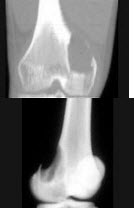

C.房间隔缺损

115、单项选择题

男,22岁,左侧膝部肿胀,疼痛2月余,结合影像学检查,最可能的诊断是()

A.骨脓肿

B.骨肉瘤

C.骨髓炎

D.动脉瘤样骨囊肿

E.软骨肉瘤